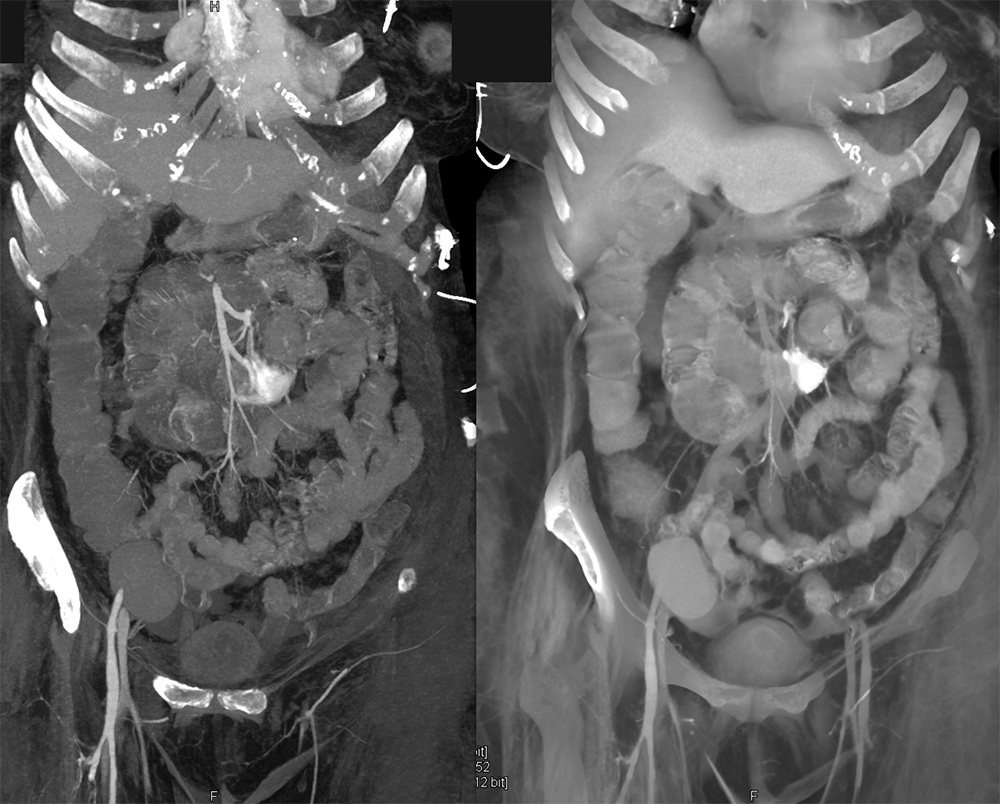

GIST Tumor Jejunum as the Cause of GI Bleeding ![]() |

![]() |

GI Bleed ![]() |